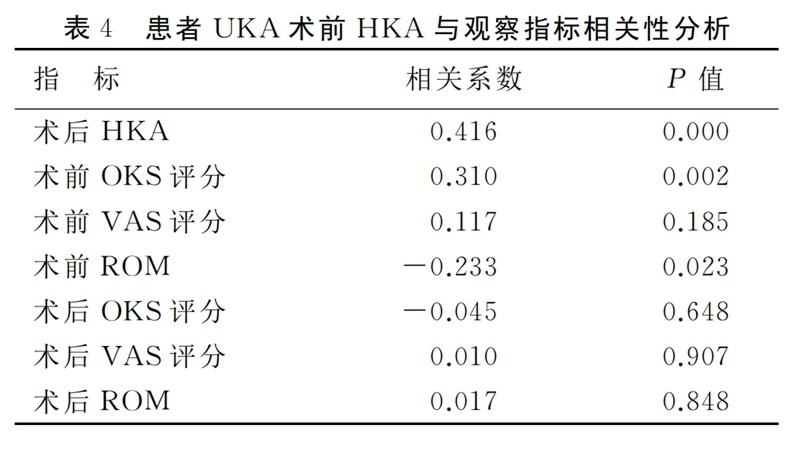

2.3 相关性分析

进一步分析术前下肢力线内翻程度与观察指标相关性,结果显示术前HKA与术后HKA、术前OKS评分和术前膝关节ROM呈显著性相关(P<0.05),见表4。

膝关节骨关节炎患者往往伴有下肢力线不同程度的改变,并且绝大部分以内翻畸形为主,原因主要与膝关节内侧关节间隙相对于外侧间隙磨损变窄有关。关节的受力由下肢力线决定,内翻畸形将会导致内侧间室受力增加、骨关节炎病程的持续进展。有研究结果显示内翻程度的增加将会使患者骨关节炎的症状加重,在本研究中证实术前不同程度内翻组别的患者在OKS评分、VAS评分及膝关节ROM上存在显著差异,并且患者的术前OKS评分和膝关节ROM与下肢内翻程度呈现显著相关性。术前患者内翻畸形程度越大,膝关节功能则越差。术前下肢力线内翻畸形程度可以作为判断患者骨关节炎程度的重要指标。

3.2 术前下肢内翻畸形对术后力线的影响

对于UKA术后下肢力线的影响因素仍存在争议。Kim对124例活动平台UKA患者术后的下肢力线研究发现,UKA术后的下肢力线与胫骨和股骨的假体组件的位置无明显关系,术后下肢力线主要取决于聚乙烯衬垫的厚度。但Zhang等人回顾性分析了122例UKA的术后下肢力线得出,患者术后下肢力线与术前下肢力线的排列及术中截骨量有关,与垫片厚度无明显关系。Mullaji等认为UKA术后患肢的下肢力线将恢复到与未患骨关节炎的对侧肢体相当的水平。本研究结果表明,患者UKA术前下肢力线排列与术后下肢力线排列有显著相关性,术前下肢力线重度内翻组患者的术后下肢力线与术前轻度内翻畸形组及中度内翻畸形组间存在显著差异,术前下内翻畸形越大的患者,UKA术后下肢力线内翻度数也越大,术前下肢力线内翻畸形程度是影响术后下肢力线的重要因素。